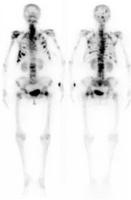

正常骨显像

全身多发骨转移

超级骨显像

肺性肥大性骨关节病